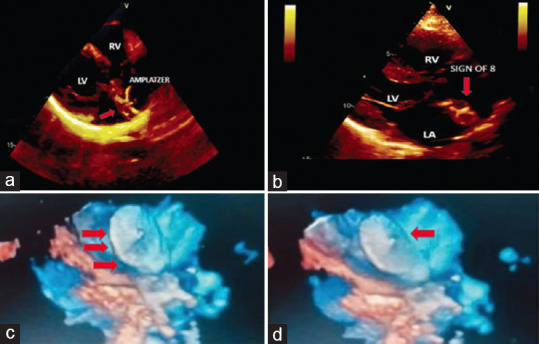

Figure-of-eight Artifact in Echocardiography as Evidence of Adequate Amplatzer Occluder Position.

超声心动图中的 "八 "字形伪影可作为 Amplatzer 封堵器位置适当的证据。